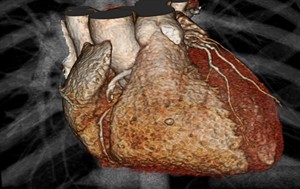

The results are a surprise: CT scans, fancy X-rays that give 3-D images of heart arteries, were expected to prove best and instead turned out to be just a reasonable alternative. Doctors have used these scans for a decade without knowing whether they are better than traditional tests. The federal government funded the $40 million study — the largest ever of heart imaging — to find out.

Chest pain can stem from something as serious as a clogged artery or as harmless as indigestion. CT scans are widely used to diagnose heart problems in emergency rooms. But their value isn’t known for people who go to a doctor with new but stable, less severe symptoms suggesting hidden heart disease.

CT scans had one advantage: more accurately guiding who needed appropriate follow-up testing and artery-opening procedures.

CT scanning “more accurately detects blockages and also more accurately excludes them,” said Duke University’s Dr. Pamela Douglas, who led the study. Deciding on a test is “a choice that doctors and patients should be making together.”